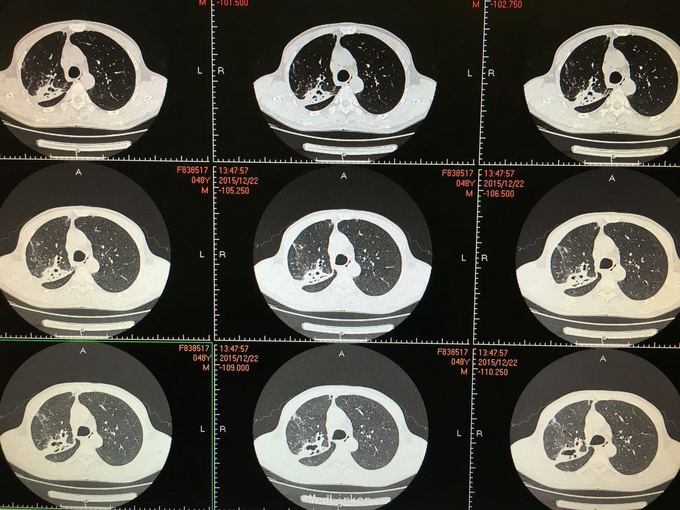

间断咳嗽咳痰5月余。患者缘于半年前确诊为骨髓增生异常综合征,并行造血干细胞移植术。术后出现发热,完善相关检查考虑为肺部真菌感染,给予抗感染治疗后体温正常,病情好转出院。出院后仍有间断咳嗽咳痰,咳黄色痰,无发热,自行口服伏立康唑200mg,2/日治疗,12月初复查CT提示双肺病灶较前进展,右肺中叶新增病灶。

根据症状体征及辅助检查,结合病史考虑真菌感染可能性大。进一步气管镜检查,结果如下。组织活检标本可见。病理回报提示真菌团,培养见曲霉菌生长。明确诊断后给予两性霉素B雾化吸入及伏立康唑静脉应用抗真菌治疗,同时给予环孢素口服。

造血干细胞移植后肺部感染常见,其中以曲霉、卡肺等多见,患者经气管镜检查已将真菌团块取出。术后给予监护,口服云南白药、垂体后叶素雾化止血等治疗,无明显出血,症状逐渐好转。复查CT也明显好转。